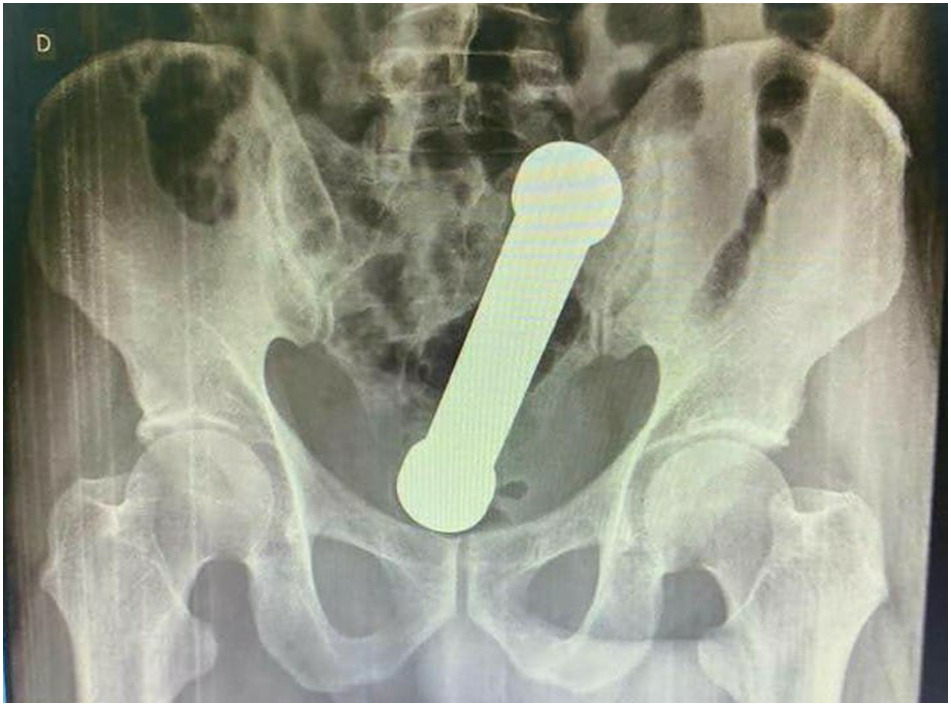

Sin embargo, las radiografías abdominales revelaron que el hombre tenía una mancuerna de 20 centímetros atorada a la altura donde el colon se conecta con el recto.

Posteriormente, el sujeto confesó que dos días antes se había introducido el objeto metálico de dos kilos sin lograr sacarlo después de su interior.